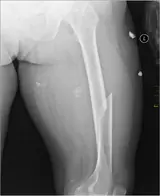

Fracture de la diaphyse femorale